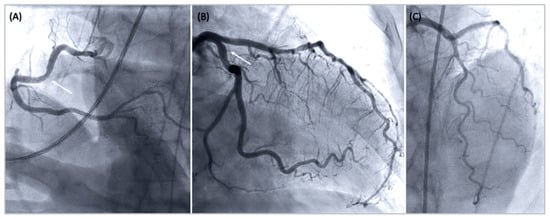

On arrival at our hospital, the patient was awake, and the ECG no longer indicated any acute abnormalities. The urgen coronary angiogram was unremarkable except for mild atherosclerosis (normal coronary blood flow, no angiographic evidence for thrombus or plaque rupture) (Figure 2). In addition, left ventriculography indicated moderate left ventricular dysfunction (ejection fraction 40%) with diffuse hypokinesia. The patient was admitted to our intensive care unit (ICU). Shortly after admission to the ICU, he started complaining of rapidly worsening chest discomfort, which was accompanied by recurrent ST-segment elevations in the anterior leads, as shown in Figure 3a. Sublingual nitroglycerine administration promptly improved both symptoms and the ECG changes (Figure 3b). Nevertheless, he developed a recurrent episode of VF secondary to early premature ventricular contractions (Figure 3c). This was immediately terminated by defibrillation at 200 joules.

Figure 2. Coronary angiogram indicating mild coronary atheromatosis (arrow): (A) right coronary artery – left anterior oblique cranial projection, (B) left circumflex – right anterior oblique caudal view, and (C) left anterior descending artery – cranial projection.